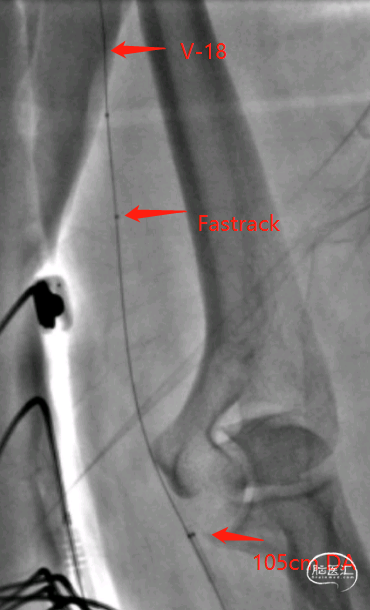

6.5F 薄壁桡动脉鞘

105cm 071 远端通路导引导管(DA)

0.018 V-18 导丝

Fastrack 微导管

成功穿刺左侧远桡动脉后,置入6.5F薄壁桡动脉鞘,V18+Fastrack微导管支撑下,DA顺利进入L-V1段。